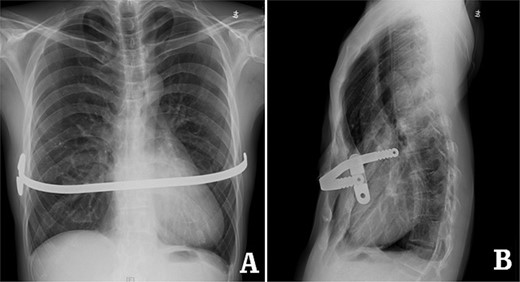

examination showed that the anterior chest wall was sunken and uneven in the middle, and two scars were visible on the lateral chest wall (Fig. 1). The preoperative imaging examination showed that there was a steel bar in the chest wall, and the anterior chest wall was depressed. The lower part of the sternum was broken, with its distal end was supported up by the steel bar. The lower end of the sternum was located deep beneath the steel bar, and the heart was obviously compressed (Figs 2–5). The operation was performed under general anesthesia. Incisions were made in the middle of the depression and two sides of chest wall. After the steel bar was taken out, the adhesion behind the sternum was separated through the median incision. Wung procedure was performed with two steel bars to support the depressed lower part of sternum [4], and then, the third steel bar was used to perform Wenlin procedure to flatten the protrusion part of the rib arch [5, 6] (Figs 6 and 7). During the two procedures, Wang technique was used to fix all the steel bars [7]. After the two procedures were completed, drainage tubes were placed in bilateral thoracic cavities and median surgical field, and the incision was closed to end the operation (Fig. 8). The operation time was 90 min, and the operation was smooth without any complications. The appearance of chest wall returned to normal after the operation, and imaging examination showed that the position of steel bars was satisfactory (Figs 8 and 9). The patient was discharged 7 days after operation.

X-ray examination before operation. (A) Posteroanterior radiograph; and (B) lateral radiograph.